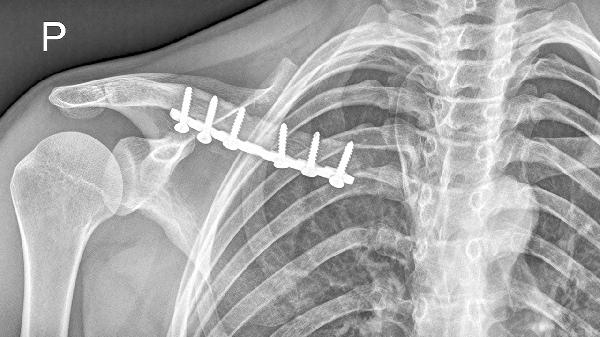

先天性发育异常可能导致锁骨或肋骨形态异常,表现为局部骨性突起。这类情况通常自幼存在,若未伴随血管神经压迫症状可暂不处理,但需定期复查观察变化。外伤后锁骨骨折畸形愈合是常见诱因,尤其见于青少年锁骨中段骨折后过度骨痂形成,可通过三维CT重建评估愈合情况,严重畸形影响功能时需手术矫正。